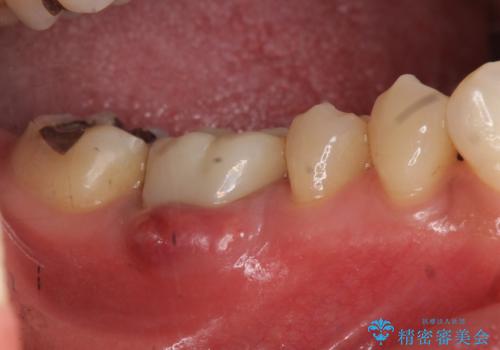

初めての根の治療には見えないくらい、かなり歯が削ってあり、薄くなっていて割れても仕方ない状態でした。前の状態を見ていないので何とも言い難いですが、他の歯に比べこの歯だけ極端に状態が悪かったです。

当院は最後まで歯を残せるように、きちんと破折していないかチェックし、患者様に写真を確認していただいたうえで抜歯をするかを相談していきます。